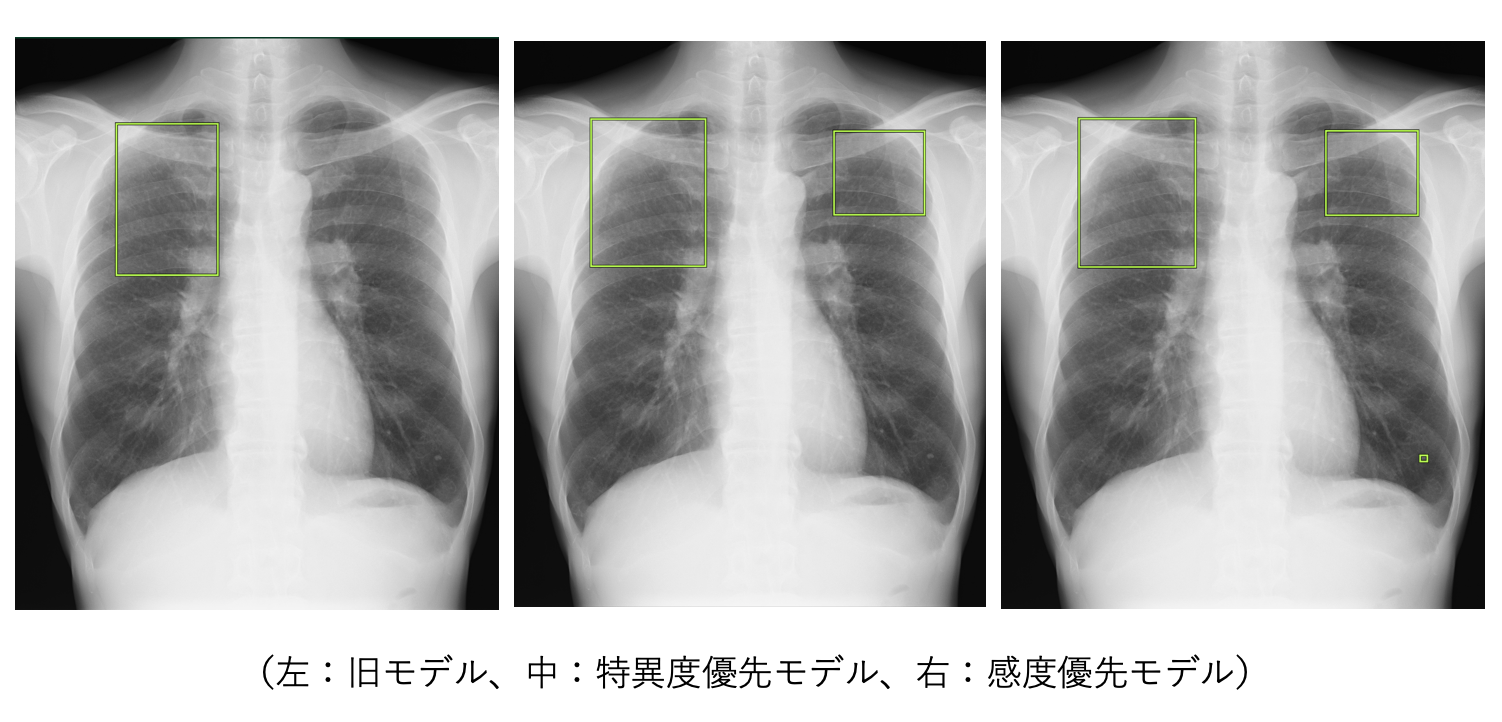

医療AI] 胸部X線CADサービス | 富士フイルム [日本]。胸部X線画像の読影診断を支援するEIRL Chest Screening、感度優先。コニカミノルタ、AIで医師の負担軽減に寄与する胸部X線画像診断支援。実践的症例レビューを通じて胸部画像診断を習得できる書籍です。。気管支の枝読みで考える 胸部画像診断入門 ── 肺既存構造と区域解剖。- タイトル: 胸部の画像診断- 英語タイトル: Thoracic Imaging- 編者: 高橋和人- 内容: 実践的症例レビューご覧いただきありがとうございます。【裁断済み】眼科疾患 最新の治療 2025-2027

• 胸部X線画像の読影診断を支援するEIRL Chest Screening、感度優先

• コニカミノルタ、AIで医師の負担軽減に寄与する胸部X線画像診断支援